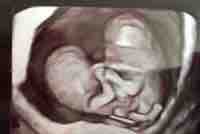

My name is Chelsea and I am pregnant with conjoined twins named Callie and Carter. They are conjoined at the lower stomach and pelvic area. We had found on June 17th 2016 I was pregnant, a few days before my sons third birthday. We had an ultrasound at 5 weeks due to cramping and the doctor told me I was miscarrying. I left in tears and was completely torn, they watched my blood levels for 6 days. I got a call on the sixth day saying my blood levels were going up but we're low, they also told me my pregnancy was close to my cervix and wouldn't last. I waited for a miscarriage. Once 8 weeks hit we had an ultrasound at a different clinic and I seen the heart beat. I cried in excitement and told the tech I was crying because I was happy. I didn't watch the rest of the screen because I knew it would be measurement and I talked with my husband because I knew the baby was just a little blob still. The tech didn't say much, she left and the doctor came in. "Are you bleeding or cramping?" I answered no, I knew something was wrong.. "well your kids are stuck together", I wish I could tell you where my mind went, It was a blur after that.. The little information I retained was "you will miscarry soon". I went to a MFM in Boise two weeks after that basing it off a scare with mono mono twins. The MFM tech started the ultrasound and there they were, together. I waited for the doctor to come in before I worried myself more. He comes in and looks at the screen, talking to the tech "there's the bind" and I knew the "bind" wasn't something small. They gave me pamphlets, gave me options, and also gave me a chance to talk to a surgeon who was from Texas. We came back the following day to talk to the surgeon, he gave us about a 20-30% chance and the doctors gave us the option to terminate. If the babies did make it (which the surgeon was optimistic about it) we would go to Texas around 20 weeks for testing. There was no way I could terminate, the thought of termination for the three days after the appointment would bring me to tears. I cried about every hour those three days after the MFM appointment.

We are currently in Eastern Idaho and for our twins to have a fighting chance, we are needing to go to Houston for testing and delivery. We have Idaho insurance and as some of the amount is paid for, but a big percentage isn't covered for out of state care. The testing would consider an echocardiogram, MRI, and extensive ultrasound. From what the doctors have told us is there is two hearts, stomachs, and spines. From the ultrasound at the Boise MFM, we were told there was two pelvises, but with the recent ultrasound (14 weeks from MFM in SLC), we were told the pelvises might be fused or there is just one. We would need to go to Houston for better imaging and getting the correct answers we need with an experienced hospital. My husband and I are in our early 20's and don't have a lifetime of savings. Before the pregnancy, my husband was working part time as I was taking 16 credit hours in college while we switched off taking care of our 3 year old son. Due to the nature of events that keep happening (subchorionic hemorrhages and needing a stress free pregnancy) and the doctors visits, I am once again not able to be employed. To keep up with Callie and Carter's journey, we have a facebook page which we update after every appointment called "Beating the odds with Callie and Carter". Thank you for becoming apart of our journey.